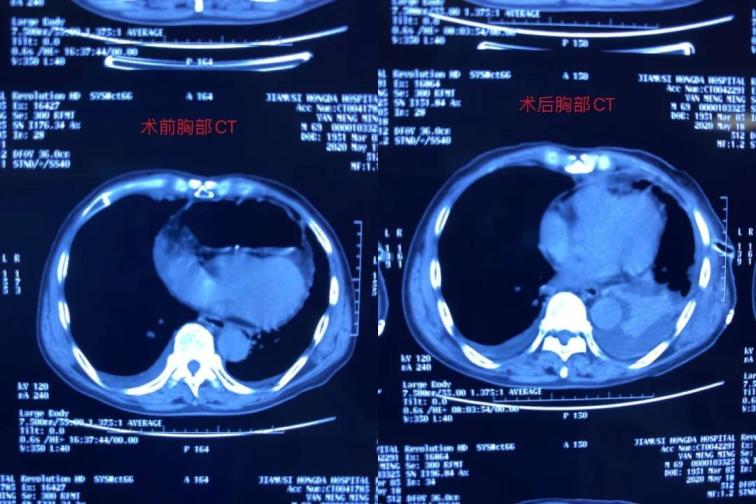

雖然患者表現(xiàn)為腸梗阻癥狀,但是從事普外多年、細(xì)心的張醫(yī)生對患者的胸部CT心前區(qū)顯示低密度影像產(chǎn)生疑問,懷疑膈疝可能,并于5月12日晨找胸外科周鋼主任會診。 周鋼主任結(jié)合病史、癥狀、查體、輔助檢查,高度懷疑膈疝中的心膈角疝,疝內(nèi)容物考慮結(jié)腸可能,因患者目前表現(xiàn)為腸梗阻,腸管卡壓時間長易導(dǎo)致壞死,且胸部CT表現(xiàn)心包填塞,此時動脈血壓已經(jīng)下降,靜脈血壓升高,脈壓差縮小,已經(jīng)出現(xiàn)休克。

術(shù)中發(fā)現(xiàn)橫結(jié)腸疝入心包并嵌頓,腸管高度擴張,已經(jīng)顏色較暗,同時疝入心包腔內(nèi)還有大網(wǎng)膜,已表現(xiàn)血運障礙。心臟嚴(yán)重受壓,近乎停止跳動。緊急切開擴大疝環(huán),觀察疝入的腸管和大網(wǎng)膜血運情況,約觀察30分鐘血運障礙恢復(fù)后,小心將疝入的腸管和大網(wǎng)膜還納入腹腔。心包腔恢復(fù)原有空間,心臟開始恢復(fù)節(jié)律性跳動。術(shù)后病人轉(zhuǎn)入胸外科病房,監(jiān)護(hù)綜合治療護(hù)理,目前患者恢復(fù)良好。

胸腹腔疝多為膈疝,疝入部位為胸腔,未見有疝入心包內(nèi)、壓迫心臟的病歷。正常心包腔內(nèi)除心臟外無容納空間,罕見腹腔臟器疝入。此患者屬罕見病例,搶救成功的關(guān)鍵在于多學(xué)科的合作、手術(shù)的及時,否則心包填塞可隨時導(dǎo)致心臟驟停甚至死亡。